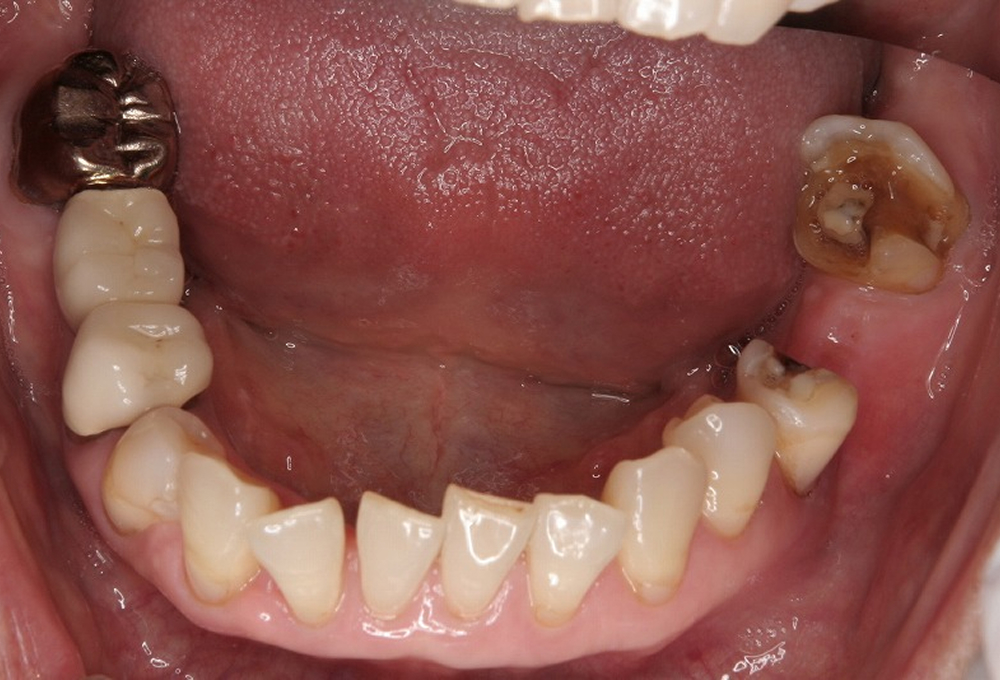

③術前下顎